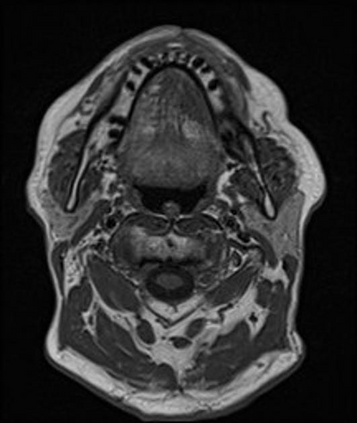

In this study, we aim to initiate the development of Radiology Foundation Model, termed as RadFM.We consider the construction of foundational models from the perspectives of data, model design, and evaluation thoroughly. Our contribution can be concluded as follows: (i), we construct a large-scale Medical Multi-modal Dataset, MedMD, consisting of 16M 2D and 3D medical scans. To the best of our knowledge, this is the first multi-modal dataset containing 3D medical scans. (ii), We propose an architecture that enables visually conditioned generative pre-training, allowing for the integration of text input interleaved with 2D or 3D medical scans to generate response for diverse radiologic tasks. The model was initially pre-trained on MedMD and subsequently domain-specific fine-tuned on RadMD, a radiologic cleaned version of MedMD, containing 3M radiologic visual-language pairs. (iii), we propose a new evaluation benchmark that comprises five tasks, aiming to comprehensively assess the capability of foundation models in handling practical clinical problems. Our experimental results confirm that RadFM significantly outperforms existing multi-modal foundation models. The codes, data, and model checkpoint will all be made publicly available to promote further research and development in the field.